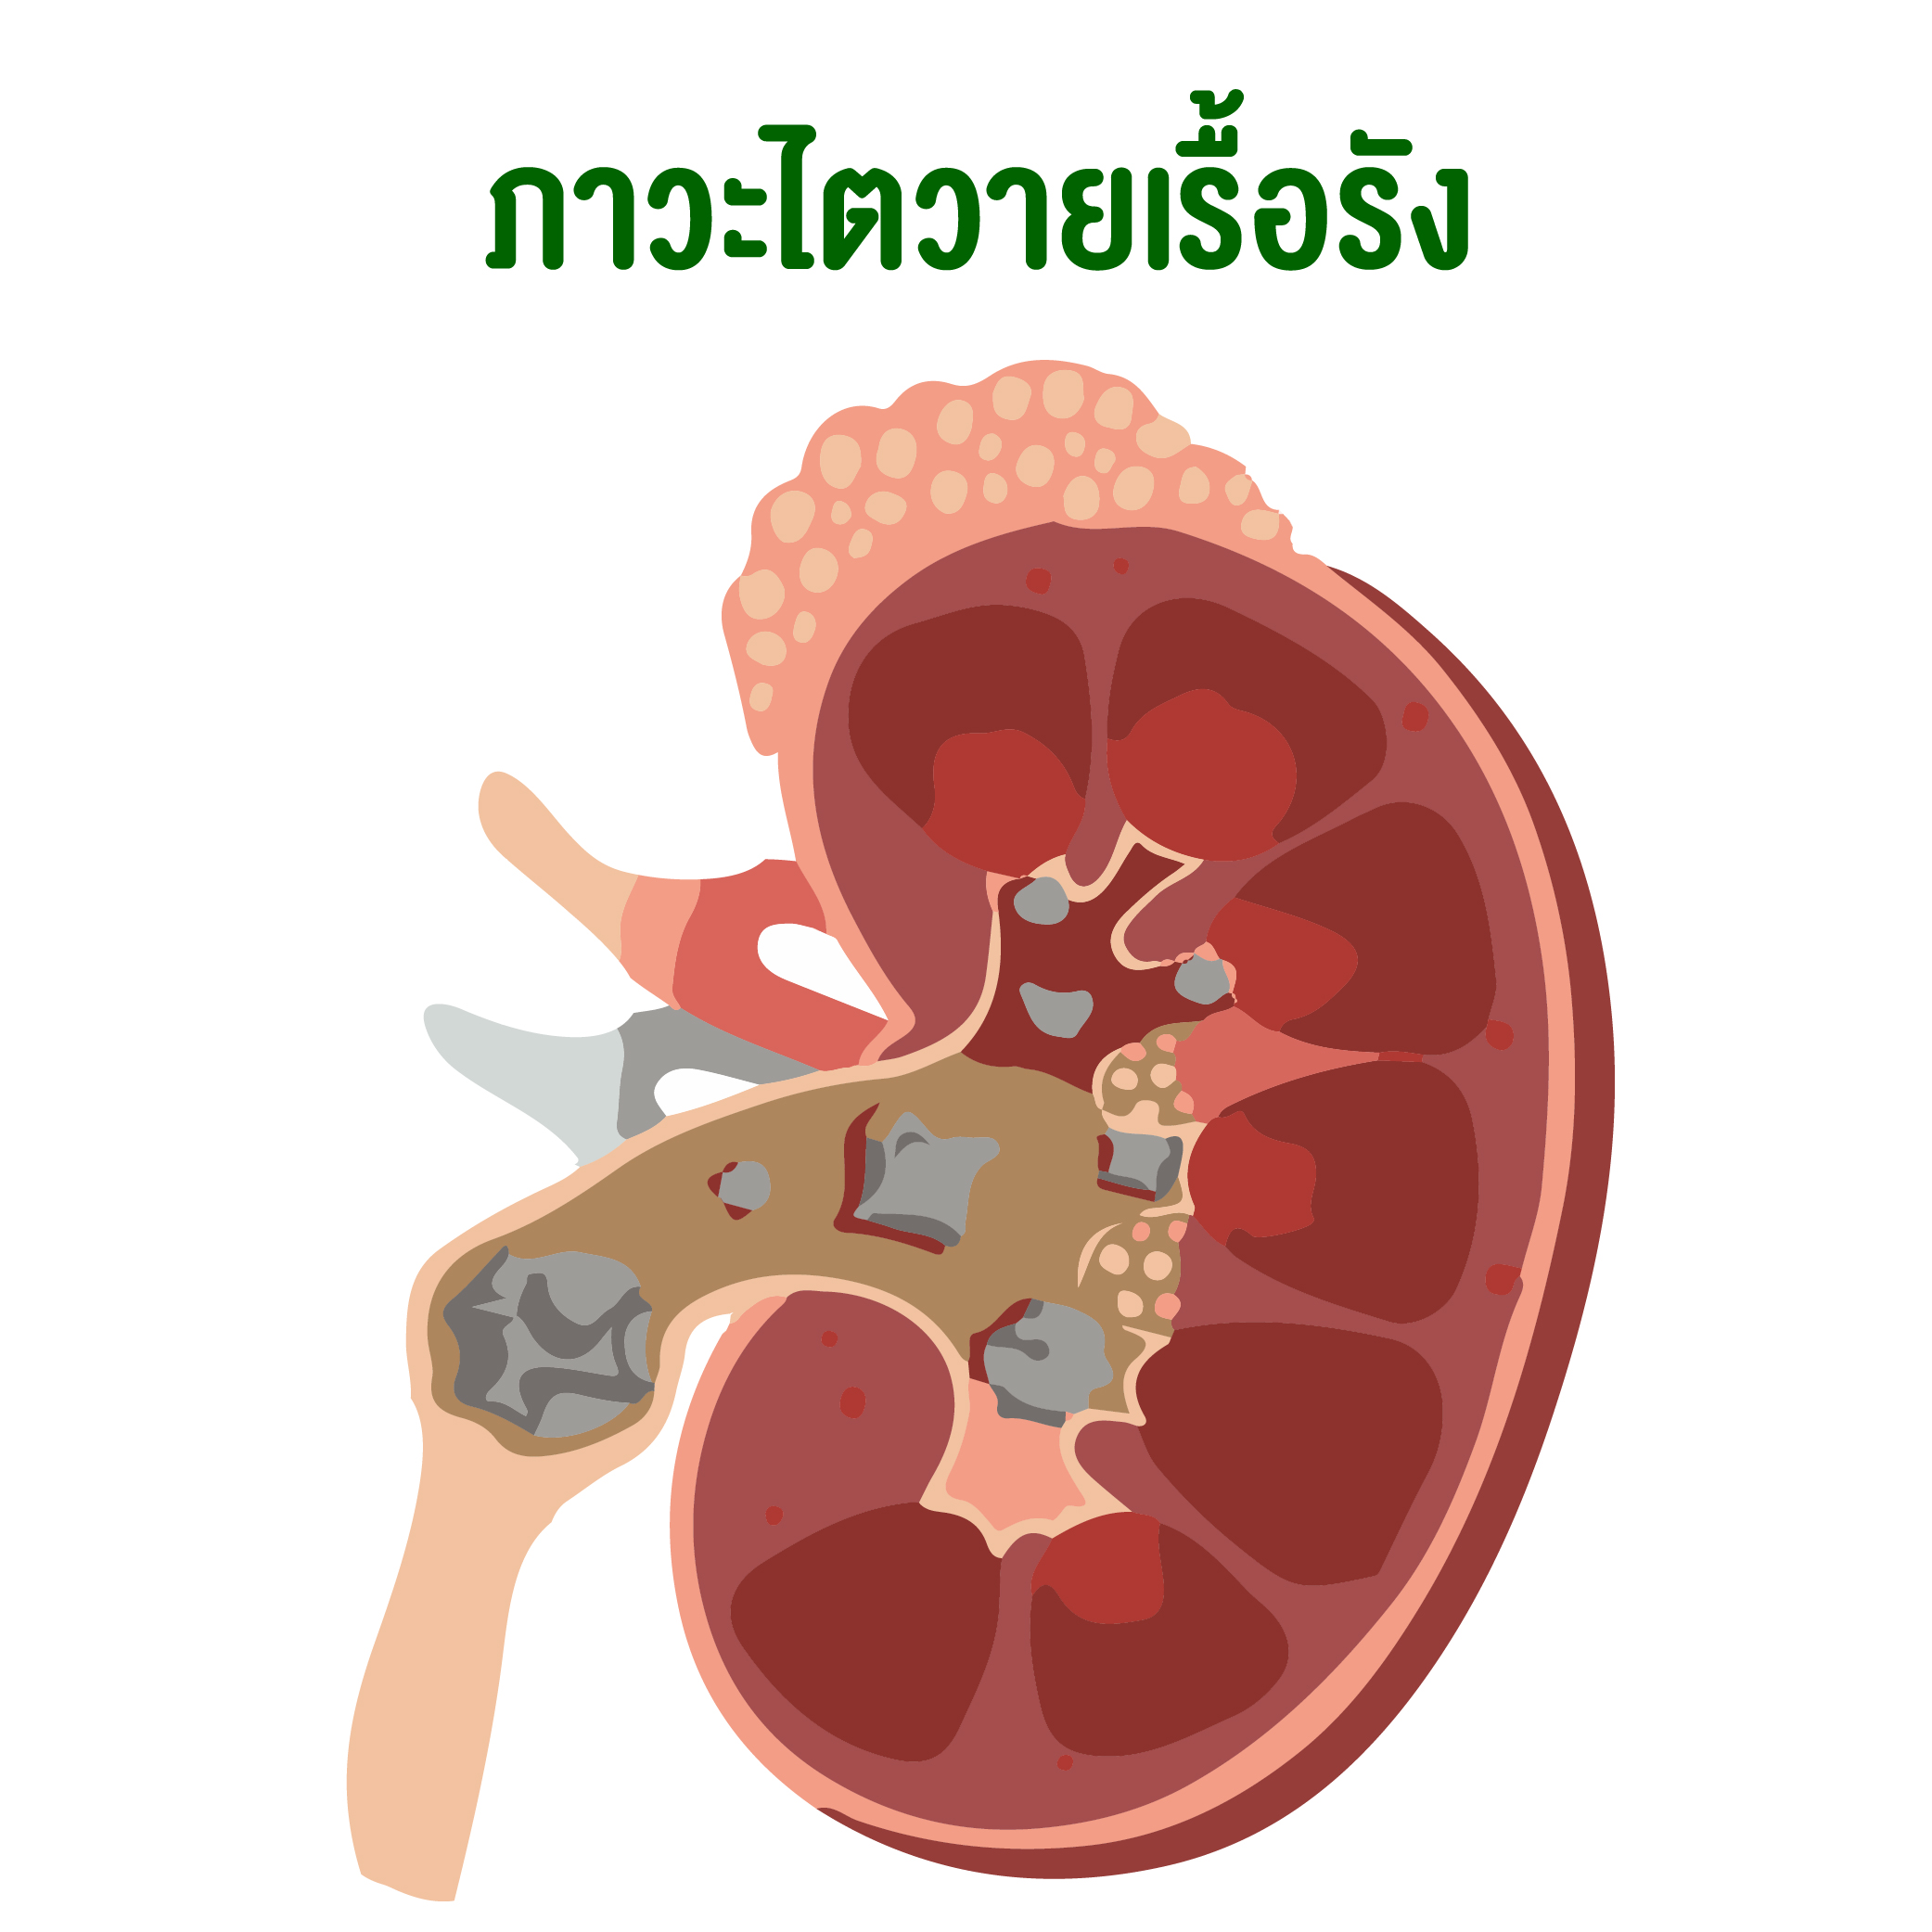

ไตวาย : ภาวะไตวายเฉียบพลันในผู้ป่วย icu เกือบทั้งหมดเกิดจากปัจจัยหลาย … ระบบหมุนเวียนโลหิตในร่างกายมนุษย์, ระบบทางเดินอาหาร, อวัยวะของมนุษย์ …